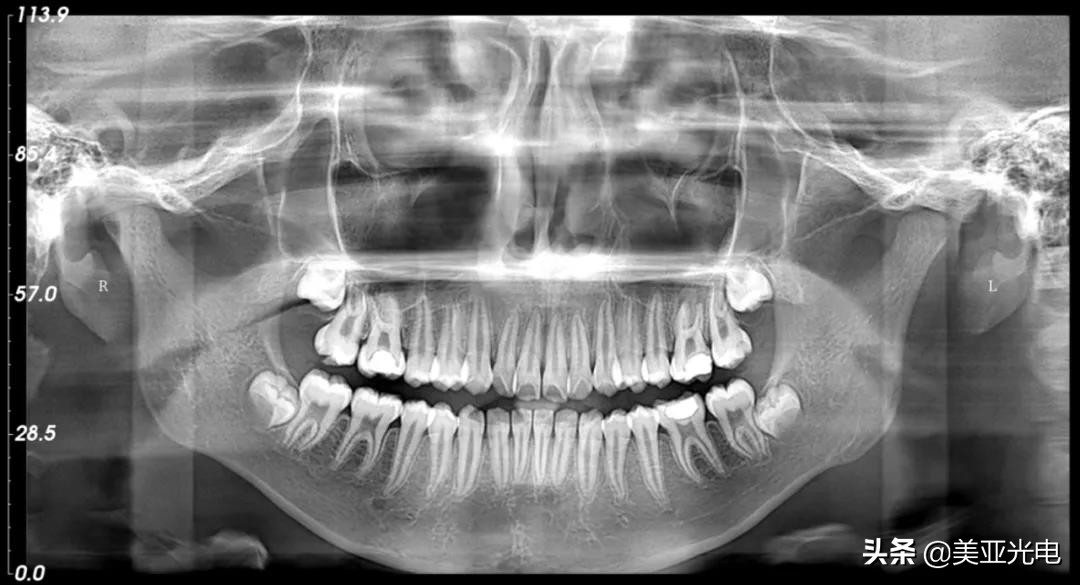

持续热销的背后,是全新一代美亚口腔CBCT优异品质的加持。2020年,标配智能全景、智能降噪、智能去伪影等硬核功能,配合自主研发超脑AI正畸分析系统和智能3D诊断软件,为口腔种植、正畸、根管治疗、颌面外科等临床诊疗提供有力支持,操作更高效,影像更精准。

▲美亚口腔CBCT—全景